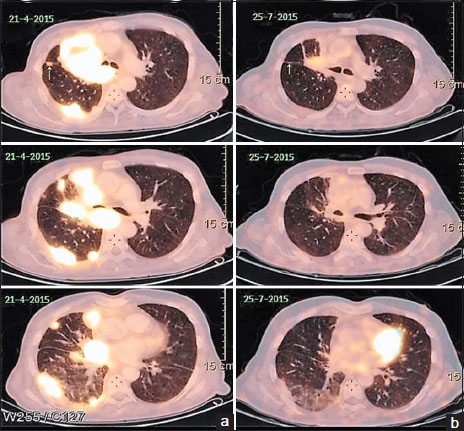

He had an excellent clinical response to the first cycle of chemotherapy and was thus given six cycles followed by 4 weekly maintenance with single-agent pemetrexed. After the third cycle of maintenance, he developed progressive disease which was confirmed by an 18-fluorodeoxyglucose positron emission tomography (PET) scan. He was started on erlotinib 150 mg/day to which there was no response. The PET scan done at 8 weeks was suggestive of progressive disease [Figure 1]a with a heterogeneously enhancing mass lesion 7.9 cm × 5.5 cm × 7.5 cm (previously 5.9 cm × 4.6 cm × 7 cm) in the right suprahilar region, pulmonary parenchymal, mediastinal lymph nodal, and solitary skeletal metastases and right pleural effusion. The patient was not receiving any medications that might change the serum levels of the EGFR inhibitors, such as CYP3A4 inducers or inhibitors.{Figure 1}

| Figure 1:(a) Left-sided images showing positron emission tomography scan revealing right suprahilar mass lesion with pulmonary parenchymal involvement after erlotinib therapy and before the start of gefitinib. (b) Right-sided images showing positron emission tomography scan done 3 months after institution of gefitinib showing partial response

He was started on gefitinib 250 mg a day. Within 2 weeks, he reported significant clinical improvement. A PET scan done 3 months later revealed partial response with marked resolution of the lung lesions [Figure 1]b. The patient exhibited excellent radiological and clinical response to the drug. The response lasted for 14 months when unfortunately the disease progressed. He died 3 months later after disease progression (no additional mutation or T790 mutation detected on repeat biopsy) after failing to respond to afatinib and nivolumab as salvage therapies.